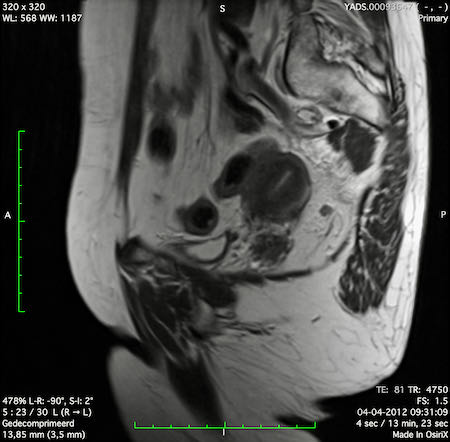

Hình ảnh

Các hình ảnh được cung cấp cho thấy ung thư biểu mô tế bào nhẫn với tình trạng dày lan tỏa thành trực tràng, hình ảnh bia bắn điển hình, và sự xâm lấn mỡ mạc treo trực tràng.